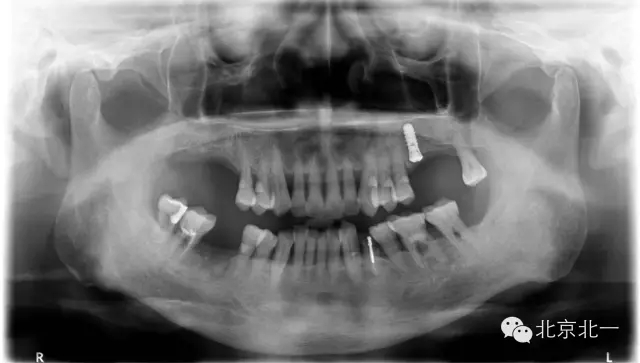

種植問(wèn)題病例一例

注:每周固定分享一例由北一種植王明老師收集到100例口腔種植問(wèn)題病例分析。

目的:和更多種植同行一起成長(zhǎng),進(jìn)步,促進(jìn)口腔種植專業(yè)健康發(fā)展,幫助年輕種植醫(yī)生規(guī)范口腔種植技術(shù),提供經(jīng)驗(yàn)與教訓(xùn),減少年輕種植醫(yī)生的專業(yè)錯(cuò)誤。

病例來(lái)源:100例病例中有自己的失敗病例,有同學(xué)分享的失敗或者問(wèn)題病例,也有學(xué)生的失敗病例,也有大學(xué)院校的失敗病例,也有微信微博分享出來(lái)收集的失敗或者問(wèn)題病例,如有版權(quán)爭(zhēng)議請(qǐng)告知小編會(huì)及時(shí)安排刪除。

編號(hào)027號(hào)

患者取模,最后無(wú)法脫模,和患者采用石膏取模異曲同工之妙!

分析:患者牙周病,前牙區(qū)間隙大, 倒凹明顯, 醫(yī)生沒(méi)有注意填倒凹導(dǎo)致無(wú)法脫模, 最后用手術(shù)刀破壞硅橡膠,鋼絲剪剪斷托盤(pán)后方取下托盤(pán)。非常慶幸不是鋼托盤(pán)呀!

預(yù)防措施:取模前切記要充填倒凹即可,特別是牙周病患者,至于什么材料充填可以很多選擇, 最簡(jiǎn)單方便的就是蠟片。